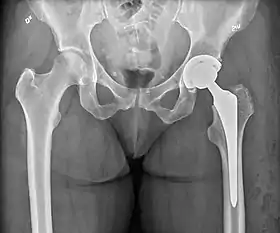

X-ray of the hips, with a right-sided hemiarthroplasty